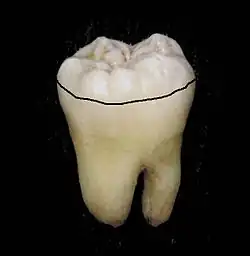

Zahnäquator

Der Zahnäquator ist der größte Umfang eines Zahnes im Bereich der Zahnkrone.

Man unterscheidet zwischen dem anatomischen Zahnäquator (das ist der größte Umfang einer Zahnkrone, bezogen auf die Zahnlängsachse) und dem prothetischen Zahnäquator (das ist der größte Umfang einer Zahnkrone, bezogen auf die Einschubrichtung einer Teilprothese).

Der anatomische Zahnäquator liegt (bei Unterkiefermolaren) etwa 2 mm oberhalb des Zahnfleischrandes (bei Oberkiefermolaren entsprechend etwa 2 mm unterhalb). Approximal berührt der Zahnäquator punktartig die Nachbarzähne (Kontaktpunkt).